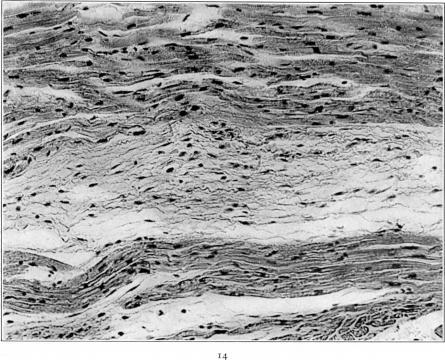

Studies on the Myocardial Aschoff Body: I. Descriptive Classification of Lesions.

Am J Pathol. 1934 Jul;10(4):467-488.15.

Studies on the Myocardial Aschoff Body: I. Descriptive Classification of Lesions.心肌阿绍夫小体的研究:I. 病变的描述性分类